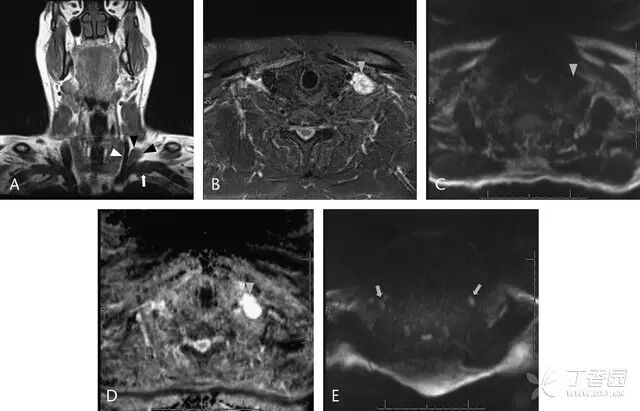

图 1  颈部 MRI 图像:A,冠状面 T1 序列显示左侧颈内静脉(白短箭头)和锁骨下静脉(白长箭头)交汇处可见一低信号肿物(黑短箭头);B,轴位短时反转恢复序列显示此肿物 T2 高信号(灰短箭头);C~E 为 DWI 和 ADC 成像,显示肿物未表现弥散受限(灰短箭头),这一特征可与来自其他部位的颈部淋巴结(灰箭头)相区分